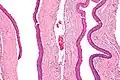

Odontogenic keratocysts have a diagnostic histological appearance. Under the microscope, OKCs vaguely resemble keratinized squamous epithelium;[15] however, they lack rete ridges and often have an artifactual separation from their basement membrane.[2]

The fibrous wall of the cyst is usually thin and uninflamed. The epithelial lining is thin with even thickness and parakeratinised with columnar cells in the basal layer which have focal reverse polarisation (nuclei are on the opposite pole of the cell).[13] The basal cells are an indication of the odontogenic origin as they resemble pre-ameloblasts. The epithelium can separate from the wall, resulting in islands of epithelium. These can go on to form 'satellite' or 'daughter' cysts, leading to an overall multilocular cyst.[10] Presence of daughter cysts is particularly seen in those with NBCCS.[13] Inflamed cysts show hyperplastic epithelium which is no longer characteristic of OKCs and can have resemblance to radicular cysts instead. Due to areas of focal inflammation, a larger biopsy is required for correct diagnosis of odontogenic keratocysts.[10]

Intermediate magnification of an odontogenic keratocyst showing a folded cyst. -